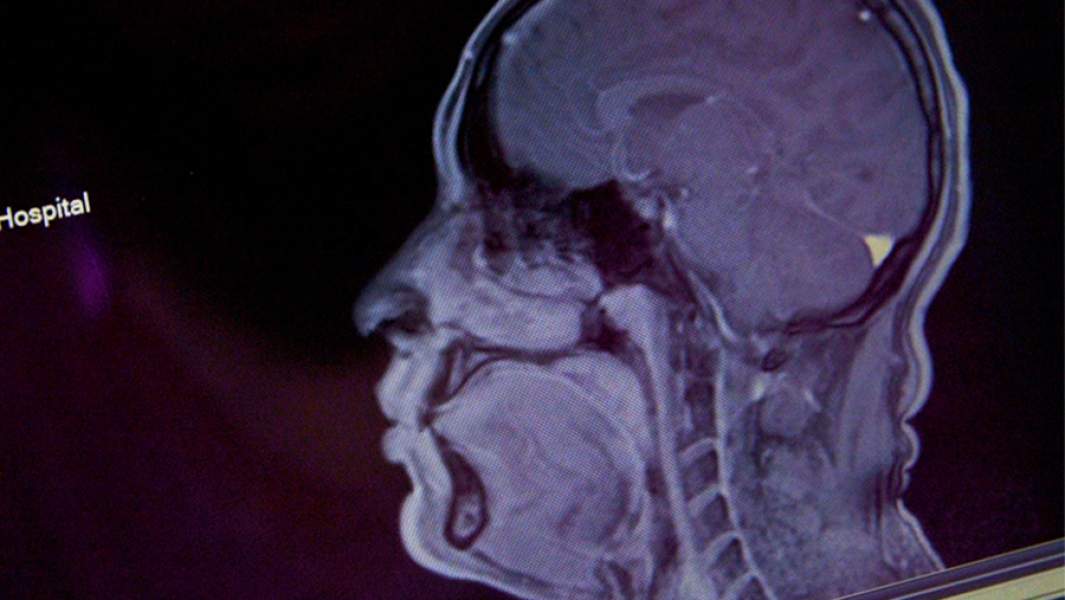

мрт

Фото: Global Look Press/John Pendygraft

Чтобы правильно установить причину потери обоняния после COVID-19, следует провести полное диагностическое обследование, включая МРТ мозга, подчеркнула эксперт. Это поможет как понять причину утраты обоняния, так и оценить степень повреждения ответственных за обоняние органов. Иногда проблема заключается в нарушении работы мозга, а не повреждении слизистой носа. В таком случае восстановление обонятельного эпителия не поможет при попытках вернуть обоняние после болезни.